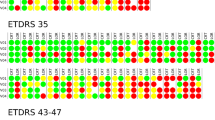

In seven patients (19.4%), SSPiM findings disappeared at approximately 5 months (range, 4–6 months). In four (11.1%) of these patients, the hyperreflective materials increased in quantity and coalesced to form hard exudates (Figs. 2 and 3). In the other three patients (8.3%), SSPiM resolved without the formation of any hyperreflective material or hard exudate at the edge of the hyperreflective fluid. In some eyes, SSPiM disappeared from one site but was later detected in another area during follow-up. The clinical and anatomical characteristics of patients with SSPiM are examined according to DR type in Table 2.

Conversion of SSPiM to hard exudate over time. Case 3: A 45-year-old man with type 2 DM for 7 years. a En-face OCTA (upper left) shows hyperreflectivity corresponding to the pseudo-flow signal around the FAZ (yellow circle). b B-scan image with superimposed OCTA flow signal (middle left) shows a nonvascular pseudo-flow signal shown in red. c Baseline structural B-scan OCT image (lower left) shows hyperreflective fluid accompanied by hyperreflective material (white arrow). At 6-month follow-up, d the pseudo-flow signal is no longer detected on en-face OCTA. However, the appearance of hard exudates was observed at the location of the SSPiM. e OCTA-superimposed B-scan sections (yellow arrows) f Structural B-scan sections (yellow arrows). g Multicolor imaging (yellow circle)

Conversion of SSPiM to hard exudate over time. Case 4: A 65-year-old man with type 2 DM for 21 years and PDR for 3 years. The patient had a history of panretinal laser photocoagulation, micropulse laser, and multiple intravitreal anti-VEGF injections. At 5-month follow-up, the en-face OCTA images show a decrease and disappearance of the pseudo-flow signal. a Initial en-face OCTA images. b Three-month en-face OCTA images. c Five-month en-face OCTA images. d B-scan OCT images superimposed with OCTA flow signals show hyperreflective fluid (white arrow). e In the outer nuclear layer adjacent to the outer plexiform layer at baseline, accumulation of hyperreflective material (yellow arrow) at the edge of the hyperreflective fluid at 3 months. f The appearance of a hyperreflective retinal spot larger than 30 µm with back shadowing (green arrow) due to the coalescenc of hyperreflective material at 5 months